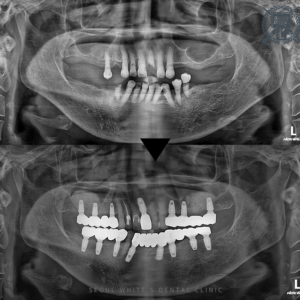

광복동임플란트, 유도골재생술을 통해 뼈이식 임플란트 사례 안녕하세요, 광복동임플란트 서울화이트S치과입니다 저희 치과를 방문해 주시는 환자분들 중 임플란트에 대해 궁금해하시는 분들이 많습니다. 그 중에서도 상악과 하악 임플란트 식립의 차이점에 대해 자주…